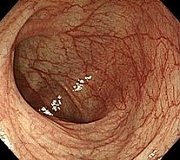

早期大腸がん